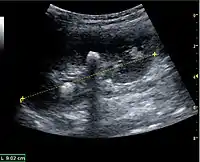

Figure 8. Cortical solid mass, which later was shown to be renal cell carcinoma. Measurement of the solid mass on the US image is illustrated by '+' and a dashed line.[1]

Figure 9. Renal cell carcinoma with both cystic and solid components located in the cortex. Measurement of tumor on the US image is illustrated by '+' and a dashed line.[1]

A solid renal mass appears in the US exam with internal echoes, without the well-defined, smooth walls seen in cysts, often with Doppler signal, and is frequently malignant or has a high malignant potential. The most common malignant renal parenchymal tumor is renal cell carcinoma (RCC), which accounts for 86% of the malignancies in the kidney. RCCs are typically isoechoic and peripherally located in the parenchyma, but can be both hypo- and hyper-echoic and are found centrally in medulla or sinus. The lesions can be multifocal and have cystic elements due to necrosis, calcifications and be multifocal (Figure 8 and Figure 9). RCC is associated with von Hippel–Lindau disease, and with tuberous sclerosis, and US has been recommended as a tool for assessment and follow-up of renal masses in these patients.[1]

However, US is not the primary modality for the evaluation of solid tumors in the kidney, and CT is the first choice modality. Nevertheless, hemorrhagic cysts can resemble RCC on CT, but they are easily distinguished with Doppler ultrasonography. In RCCs, Doppler US often shows vessels with high velocities caused by neovascularization and arteriovenous shunting. Some RCCs are hypovascular and not distinguishable with Doppler US. Therefore, renal tumors without a Doppler signal, which are not obvious simple cysts on US and CT, should be further investigated with CEUS, as CEUS is more sensitive than both Doppler US and CT for the detection of hypovascular tumors.[1]